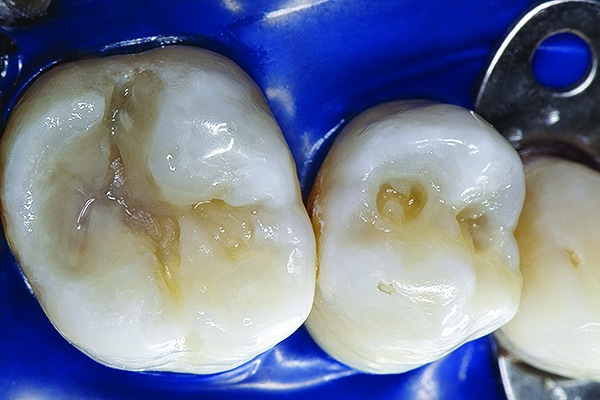

The mechanism of adhesion is similar for enamel and dentin—a micromechanical entanglement of monomers into the enamel microporosities or collagen interfibrillar spaces created by acid dissolution of mineralized tissues.45,46 When evaluating restorative success, the marginal integrity achieved by this procedure becomes a priority since an intact restorative–tooth interface is essential to the exclusion of bacteria and the interfacial hydrodynamic equilibrium of the dentino-pulpal complex (Figure 8 through Figure 11).

Figure 8. AND Figure 9. After the preparations were cleaned with 2% chlorhexidine, a selective etching of the cavosurface enamel was performed with 37.5% phosphoric acid gel for 10 seconds, rinsed for 5 seconds, and gently air dried. Notice the selective etch pattern of the enamel demonstrating a frosty appearance.

Figure 8

Figure 9